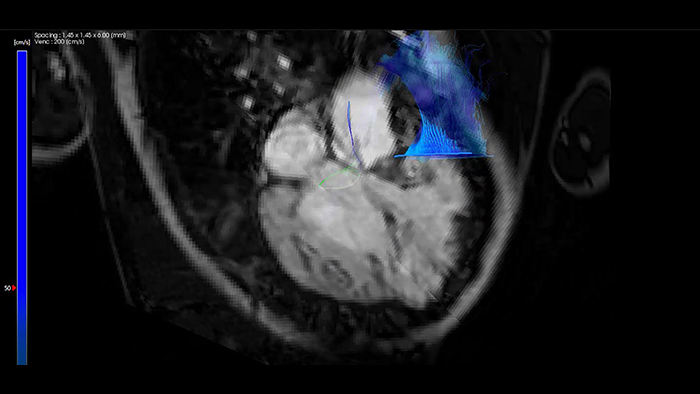

Flujo 4D de IntelliSpace Portal MR Caas en tetralogía de Fallot